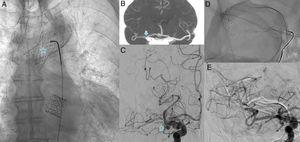

Infarto cerebral embólico de origen no determinado: más allá de la fibrilación auricular

Introducción El infarto cerebral embólico de origen no determinado (ESUS por sus siglas en inglés) representa el 25% de todos los infartos cerebrales y solo el 30% se asocia con fibrilación auricular (FA) paroxística. Existen […]